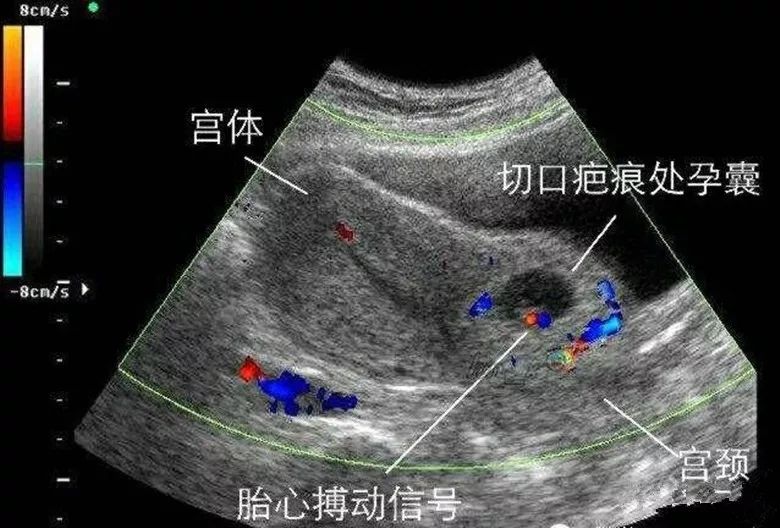

剖宫产术后子宫瘢痕部位妊娠(CSP)是一种特殊类型的异位妊娠,是指既往有剖宫产史的孕妇,此次妊娠胚胎着床于子宫下段剖宫产切口瘢痕处。以前属于罕见的异位妊娠,但随着剖宫产的增加,诊断及报道越来越多。瘢痕部位妊娠在清宫术中、术后容易出现难以控制的大出血,子宫破裂,周围器官损伤,甚至需要切除子宫,严重威胁女性生殖健康甚至危机生命。早期诊断、及时恰当的治疗,选用合适的个体方式,可避免大出血等不良后果,保留患者的生育能力。

西安市中心医院妇科对瘢痕部位妊娠的患者,已经建立了一整套针对患者具体情况的个体化诊疗方案,在保障患者生命安全的同时,最大程度的保护女性的生育力。从近期瘢痕部位妊娠四例中两例术中发现已是子宫不全破裂,而宫腔镜手术中发现的瘢痕部位憩室也绝不是罕见情况,瘢痕部位憩室是瘢痕部位妊娠的基础。提醒有过剖宫产或子宫肌瘤手术史的女性朋友们,若有妊娠可能,一定要及时到医院检查,确定孕囊位置,若出现瘢痕部位妊娠,一定要及时诊治,避免造成严重的大出血威胁生命或影响到生育能力!